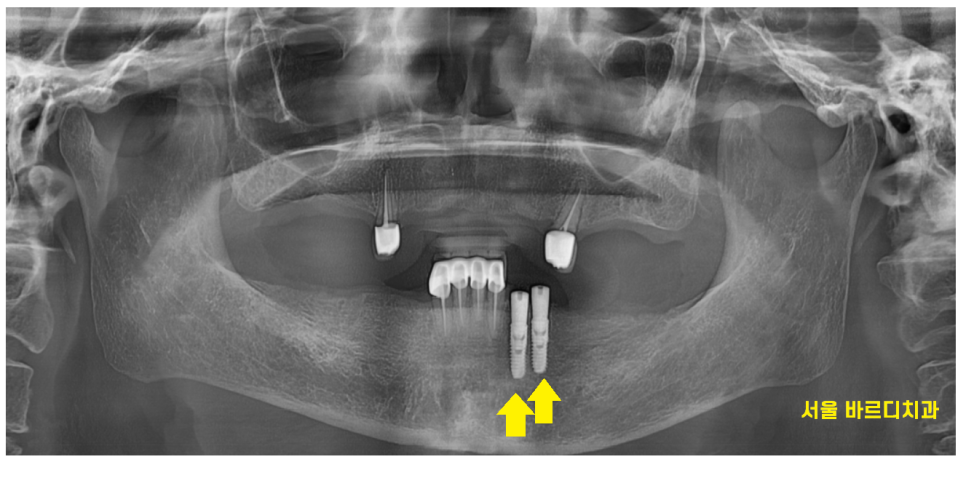

23.11.27

틀니 사용중 치아 부러짐

해결을 위해서는

부러진 정도가 중요합니다!!

환자분은 뿌리만 남았을 정도로 많이 부러져서

뽑아야했습니다.

뽑아야함을 설명드리고

보험 임플란트 2개를 해야할꺼같다 말씀드렸더니